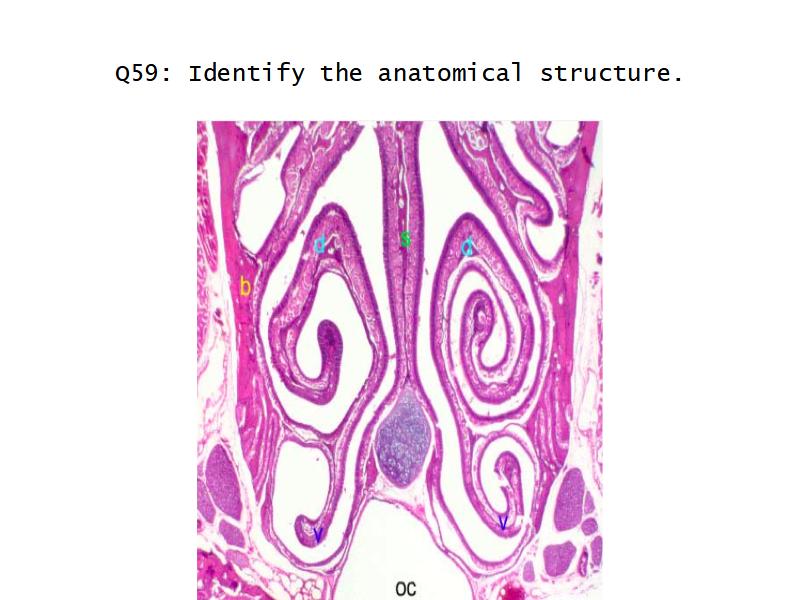

Function of the nasal cavity?

Function of the nasal cavity?

- Warm

- Moisture

- Filter

- Smell